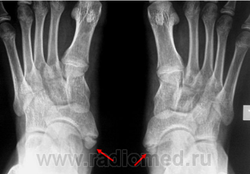

Основными методами диагностики были

клинический и рентгенологический.

дьевидной кости (рис. 1).

Рис.1. Боковая поверхность стопы с os tibiale

externum